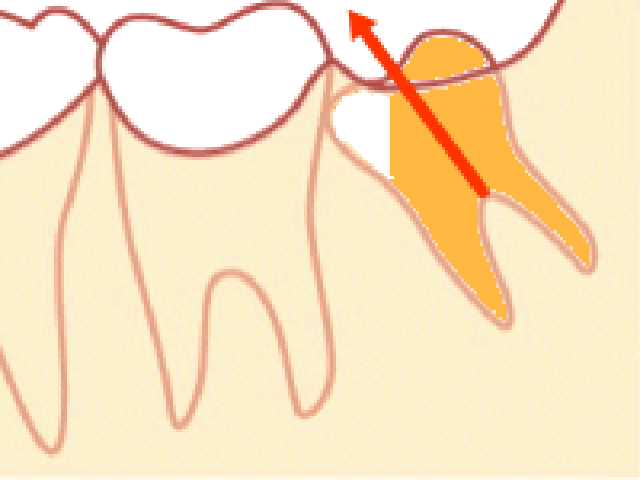

問題になることが最も多い、「斜め型」の親知らずを抜くための具体的な手順は次のようになります。

4.歯の頭を一部削ります

斜めになって前の歯にぶつかっている場合には、そのまま引っ張ってもぶつかって抜けません。そのため、抜くときにぶつからないように親知らずの歯の頭を削ります。傾きが大きいときは、この時点で歯の頭の部分を全て削ることもあります。

手前の歯にぶつかる部分をカットしてから抜く場合もございます。

歯の頭を削った後、残りの部分を取ります。

場合によっては、抜きやすいようにさらに根を2つに分けることもあります。

器具を歯の周囲に少しづつ差し込んで緩め抜きます。